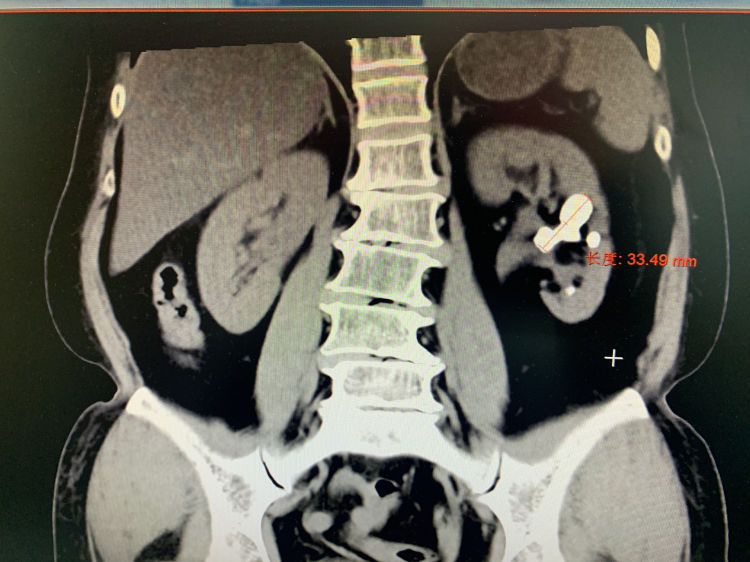

近日,一名60岁的患者,因左肾鹿角形结石(最长径3.3cm)在我院泌尿外科接受手术治疗。考虑到患者肾脏无积水且伴有多种基础疾病,如高血压、糖尿病、高血脂等,手术风险较高。为确保手术安全,泌尿外科特邀专家工作站昆医附二院李志鹏教授亲自主刀。手术虽顺利完成,但术后第四天,患者突发急性肺栓塞,左侧肺动脉主干完全栓塞,情况十分危急。